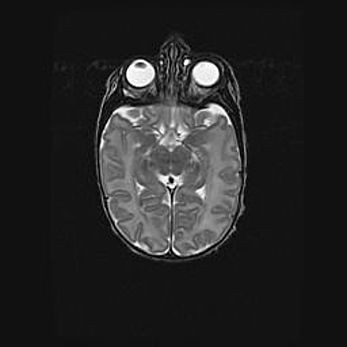

Лейкомаляция с кистозно-глиозной дегенерацией головного мозга.

Возраст: 2 месяца 25 дней

Вес: 6400 г

Окружность головы: 40 см

Срок гестации: 41 неделя

Лейкомаляцию относят к ишемически-гипоксическим повреждениям головного мозга, диагностируемым у новорожденных. При лейкомаляции в головном мозге обнаруживают очаги некроза, возникшие после тяжелой гипоксии и нарушения кровотока. В процессе морфогенеза очаги проходят три стадии: 1) развития некроза, 2) резорбции и 3) формирования глиозного рубца или кисты. Перивентрикулярная лейкомаляция (ПЛ) встречается примерно в 12% случаев среди новорожденных, обычно – у недоношенных детей, причем, частота ее зависит от массы, с которой младенец появился на свет. Наибольшее число малышей страдает лейкомаляцией, если масса при рождении 1500-2500 г.